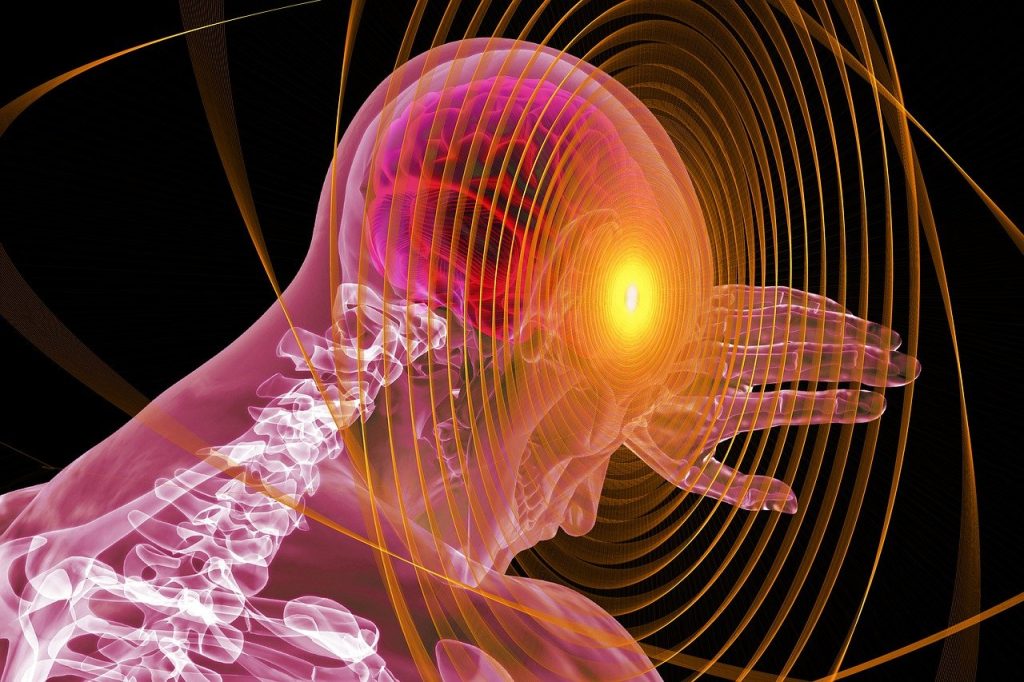

Uno studio fa luce sulle origini della schizofrenia nel cervello

Lo studio apre la strada a nuovi possibili trattamenti di questa grave patologia mentale